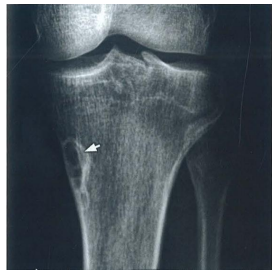

Radiografia realizada em paciente

do sexo masculino de 17 anos

demonstra a lesão radioluminescente

com bordas escleróticas apontada

pelas setas na figura. O diagnóstico

CORRETO é: